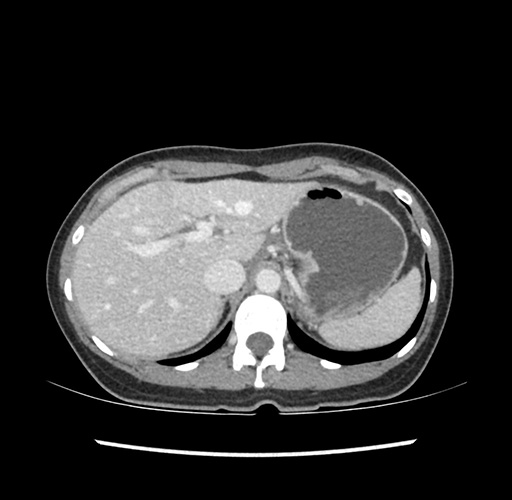

Imaging Analysis

Look through the patient's CT scan to identify any areas of concern for the necessary procedure.

Based on your CT findings, which issue(s) would give reason for "planned slowing down moment(s)" in this case?